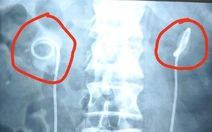

Hai ống thông để quên trong cơ thể ông L.V.E. suốt 10 năm, may mắn đã được lấy ra không gây biến chứng - Ảnh: Bệnh viện cung cấp

Bệnh nhân là ông L.V.E. (50 tuổi, ngụ phường An Xuyên, tỉnh Cà Mau). Ông cho biết hơn 10 năm trước từng được đặt 2 ống thông JJ vào niệu quản do niệu quản hai bên bị chèn ép.

Hai ngày trước, ông đến khám tại Bệnh viện Đa khoa Thanh Vũ Medic Bạc Liêu với tình trạng đau tức vùng hông lưng hai bên. Sau khi thăm khám, hỏi bệnh kỹ lưỡng và thực hiện các cận lâm sàng cần thiết, bác sĩ xác định trong người ông E. có hai ống thông JJ trong niệu quản.

Do chưa ghi nhận đứt ống hay có sỏi bám đầu ống nên bệnh viện mổ nội soi rút ống thông JJ. Hiện ông E. ổn định và đang được theo dõi sức khỏe kỹ lưỡng.